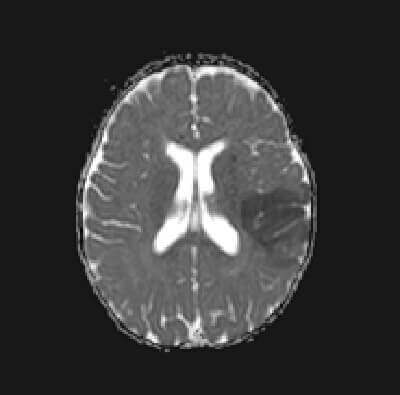

Diagnosis: MCA territory infarct

Figure 1: (a, blue arrow) increased DWI signal in the right frontal lobe is also low on ADC

b,red arrow) FLAIR images demonstrate increased cortical signal and sulcal effacement

(c, green arrow) consistent with an acute infarct.